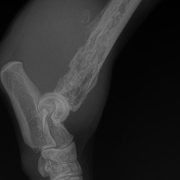

GORA crisi Destacado Crisi mèdica amb la Gora 27 agosto, 2019 por Lau GORA 27 agosto, 2019 por Lau Ver todas las entradas gorita Per novetats, deixa el teu e-mail. Escribe tu correo electrónico… Suscribirse